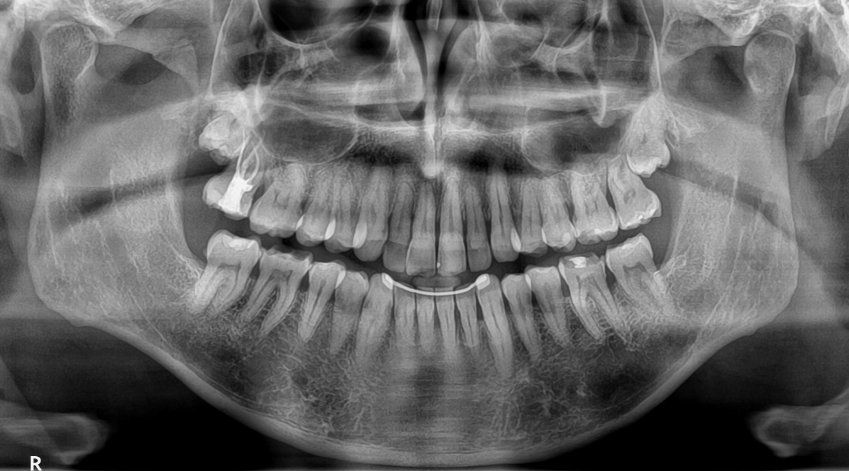

La CBCT, o Tomografía Computarizada de Haz Cónico es una técnica, de imagen en 3D que permite obtener imágenes detalladas y precisas de la estructura dental. En comparación con otras radiografías convencionales, mediante el CBCT se puede obtener una visión completa del área tratada. Esto facilita la detección de problemas que pueden pasar desapercibidas en otro tipo de pruebas mediante radiología.

En el caso de la CBCT para el tratamiento de endodoncia es especialmente útil para:

- Detectar fisuras y fracturas en los dientes.

- Distinguir conductos radiculares adicionales o complejos.

- Evaluar infecciones, abscesos o lesiones periapicales.

- Planificar retratamientos en caso de endodoncias fallidas.

Sin embargo, no en todos los casos de endodoncia es necesario su uso. Desde nuestro centro de radiodiagnóstico en Madrid, recomendamos su utilización en situaciones específicas que requieran un diagnóstico o planificación con mayor precisión. Algunos de estos casos pueden ser: dientes con anatomía compleja, reendodoncias, fracturas o fisuras radiculares o lesiones periapicales.